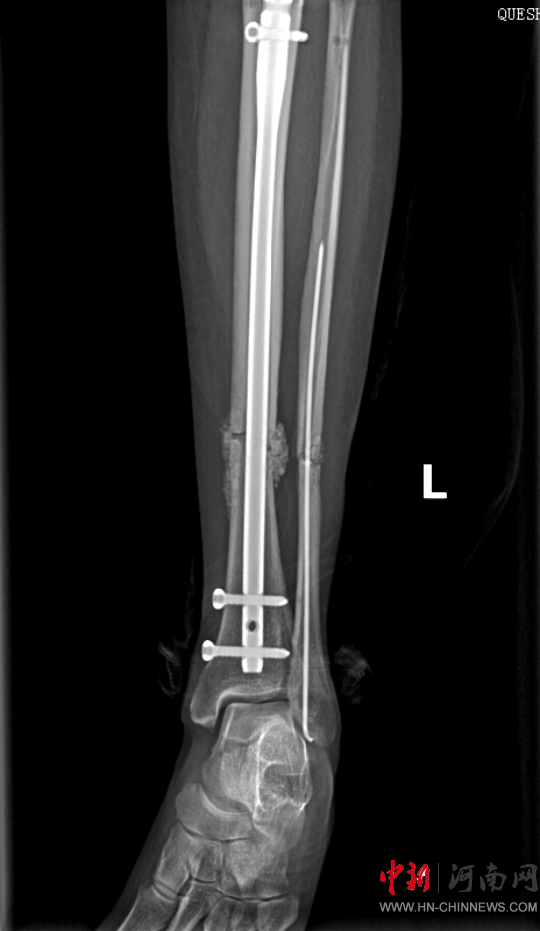

患者病情好轉(zhuǎn)后,該院急診科主任岳春彥和創(chuàng)傷治療團隊為患者制定了詳細的手術(shù)規(guī)劃,傷后第10日,患者在全身麻醉下進行“左股骨粉碎骨折及脛骨粉碎骨折髓內(nèi)釘內(nèi)固定術(shù)+骨移植術(shù)、腓骨骨折復(fù)位內(nèi)固定術(shù)”,病情平穩(wěn)后轉(zhuǎn)入急診科病房治療,切口愈合后,患者轉(zhuǎn)入康復(fù)醫(yī)學(xué)科進行腦功能康復(fù)和下肢關(guān)節(jié)康復(fù)治療。目前,患者能夠與人正常溝通交流,左下肢關(guān)節(jié)功能也恢復(fù)良好,已出院。